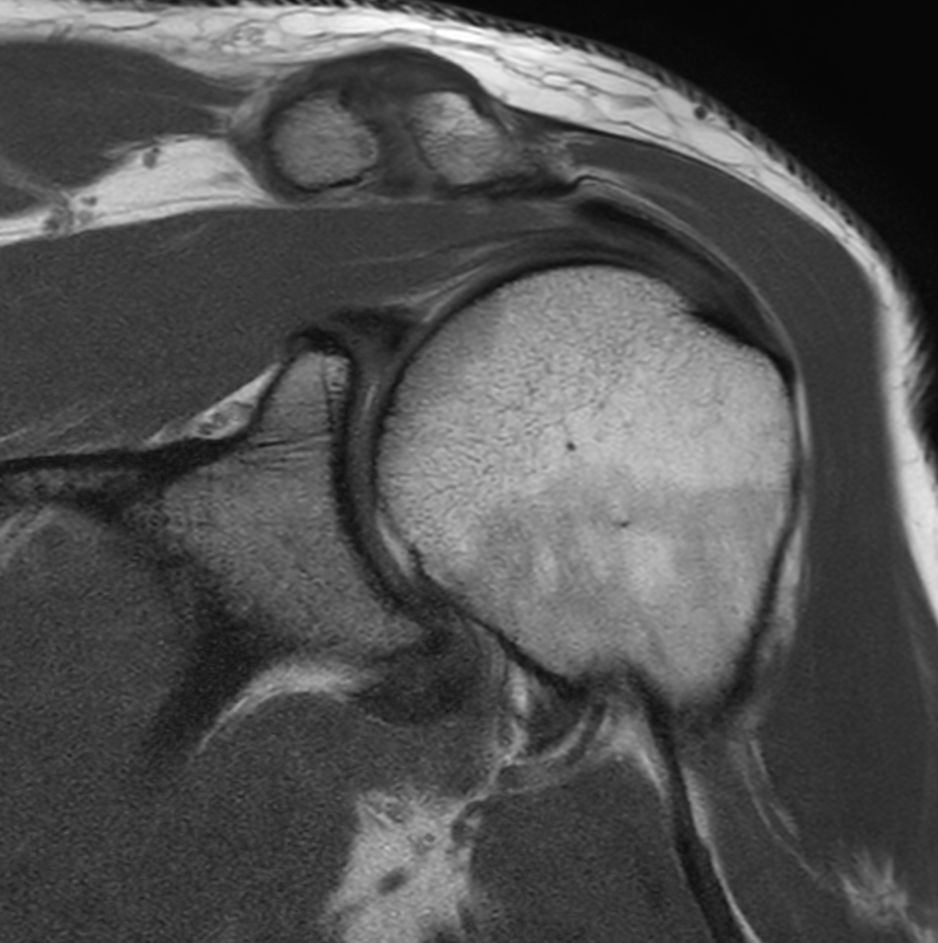

Shoulder with the dS Shoulder 16ch coil

University of Vermont Medical Center, Burlington, USA